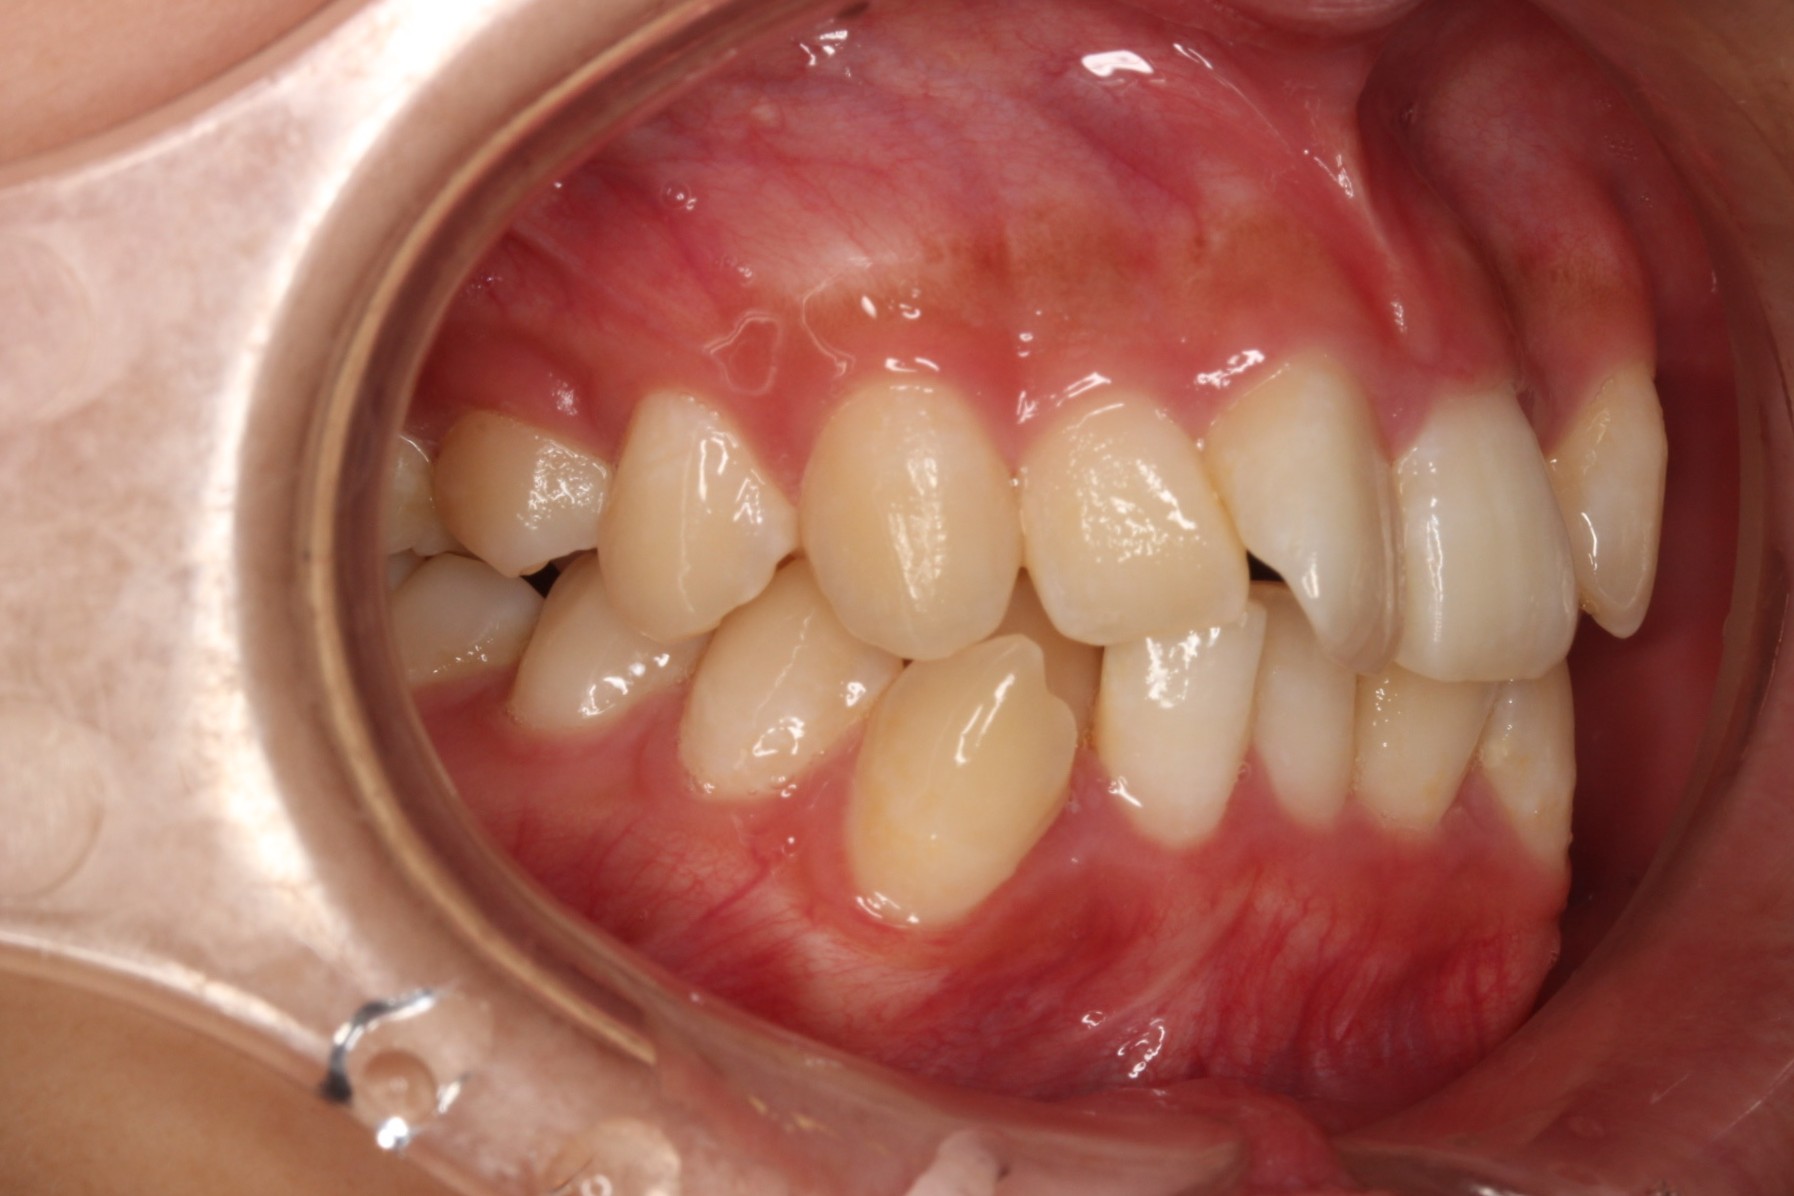

今回ご紹介する患者様は、上下のがたつきを気にされており、矯正検査後叢生Ⅰ級と診断いたしました。

矯正前に、上下小臼歯4本を抜歯いたしました。また、ワイヤー矯正後に、インビザラインで仕上げ矯正を行いました。

矯正術前:右側

| 主訴 | 上下のがたつきが気になる |

| 治療期間 | ・ワイヤー矯正:23カ月 ・インビザライン矯正:15か月 |

| 治療費用 | 1,100,000円(税込) |

| 治療内容 | 患者様は、上下のがたつきを気にされており、矯正検査後叢生Ⅰ級と診断いたしました。矯正前に、上下小臼歯4本を抜歯いたしました。また、ワイヤー矯正後に、インビザラインで仕上げ矯正を行いました。 |